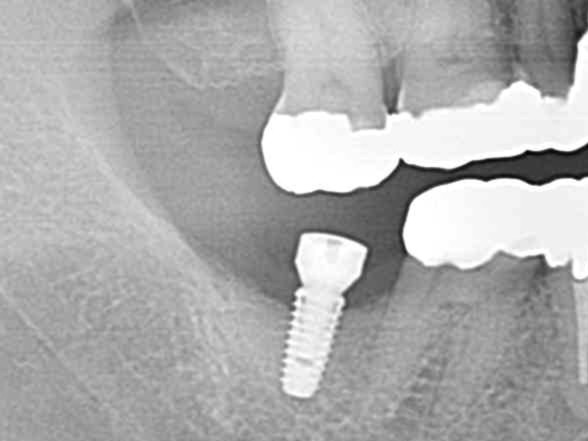

あごの骨にチタン性の人工歯根を埋め込み、噛む力を再生させる治療法です。

インプラント手術は正確な診断と治療計画、そして高度な技術を必要とします。我が国において、2007年、国が認定する

インプラント専門医制度が誕生しました。研修と業績そして試験をクリアしたものに与えられる専門医の資格です。

私も2007年度より「インプラント専門医」の資格を有しています。